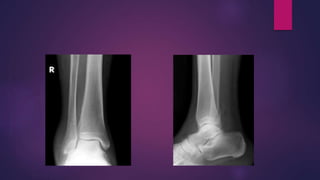

 SUPINATION ADDUCTION INJURY

SUPINATION ADDUCTION INJURY

 the traction force on the lateral ankle structures

causes

-‘pull off fracture’ of the lateral malleolus.

 Lateral malleolus fracture at the level of ankle joint.

 Characteristic transverse fracture with a ‘clean’

break in the outer fibular cortex.

 Deforming forces continue producing compression

injury of the medial malleolus

 Near vertical fracture starting in the angle

between the medial malleolus and the horizontal

tibial articular surface